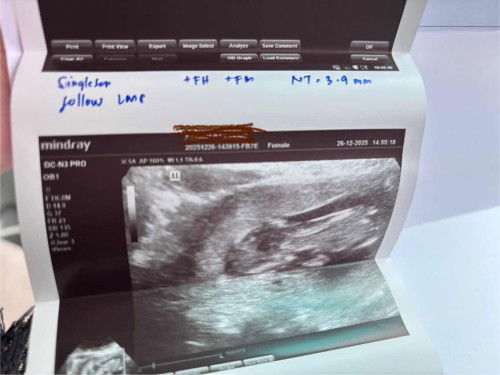

13w2d NT Scan

3.9mm detect ketebalan cecair belakang leher baby. fikiran sy risau sgt skrg ni.. dr bacaan, kemungkinan sindron atau ada masalah jantung pada baby nnti.. doktor sugest buat nipt, tp kos nya tinggi bagi saya yg kurang mampu. mohon doakan sy dan baby